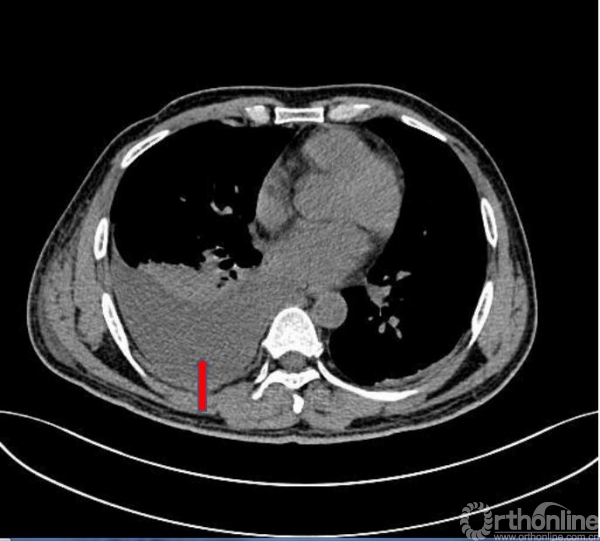

术前肺CT平扫(2017.09.17)

胸腹部CT检查

1.腹水;右侧侧锥筋膜和肾周筋膜增厚,腹膜后积血可能;腹腔脂肪间隙模糊;请结合临床;

2.右侧腰大肌异常改变,考虑挫裂伤可能;

3.右侧8-12肋骨、胸12-腰5椎体右侧横突、右侧髂骨翼骨折,周围软组织肿胀;

4.双侧胸腔积液,右侧明显。